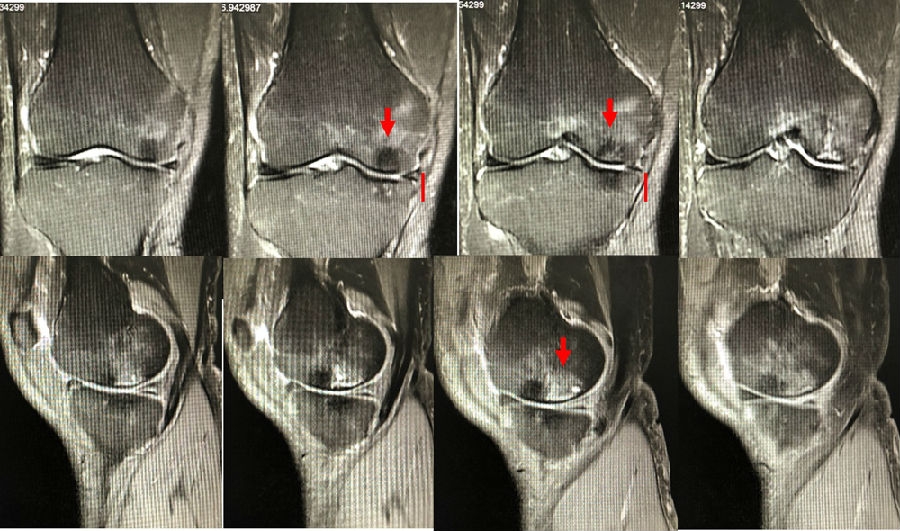

病例3:男,70岁,主诉右膝关节疼痛1年余。查体右膝无肿胀畸形,膝活动度0-120°,内侧间隙压痛。

已经累及44%的股骨内侧髁病变,半月板轻度突出,内侧后角水平撕裂

MRI上深度>20mm

治疗选择保守还是手术?

保守治疗4个月后复查

保守治疗后效果欠佳,坏死范围扩大、塌陷

翻修手术选择截骨矫形还是单髁置换?

最终选择截骨矫形

术后1年1个月

术后2年1个月拆钉

内侧半月板突出未见明显进展